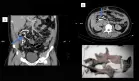

Se realizó una tomografía computarizada (TC) urgente de abdomen y pelvis, sin hallazgos sugestivos de absceso pélvico ni del psoas. Se consideraron diagnósticos diferenciales como miositis aguda y absceso intraóseo.

Una resonancia magnética (RM) de pelvis reveló edema óseo en la rama púbica izquierda y cambios inflamatorios en la sínfisis púbica compatibles con osteomielitis. La gammagrafía ósea confirmó un aumento de captación en la misma región. Posteriormente, una aspiración con aguja del hueso púbico confirmó el diagnóstico, aislando nuevamente S. viridans en el cultivo óseo.